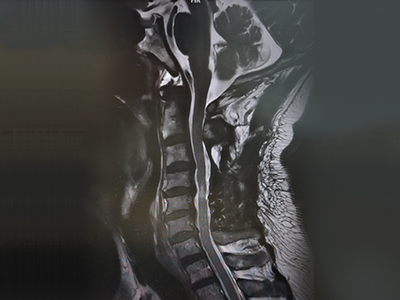

脊柱脊髓神经微创中心以微创技术为引领,以功能恢复为目标,主要治疗脊柱外伤、肿瘤、退行性病变、脊柱畸形等疾病。团队利用神经外科显微技术,结合神经内镜微创技术,对脊柱间盘变性疾病、颈腰椎管狭窄、颈腰椎间孔狭窄、颈腰椎间盘突出、颈腰椎体不稳、脊柱骨折、寰枢椎脱位、脊柱肿瘤、椎管内肿瘤、脊髓损伤、脊髓空洞、脊髓栓系等疾病进行高效、特色手术治疗,如颅颈交界区畸形寰枕减压内固定术、脊柱肿瘤全脊椎切除内固定术、微创椎管内肿瘤切除术、微创脊柱旁肿瘤切除术、寰枢椎脱位椎间融合内固定术、脊柱骨折微创经皮椎弓根钉内固定术、经椎间孔椎间融合内固定术(MIS—TLIF)等,最大程度降低脊柱脊髓手术创伤,具有创伤小、输血少、恢复快、口碑好,出院早等优势。